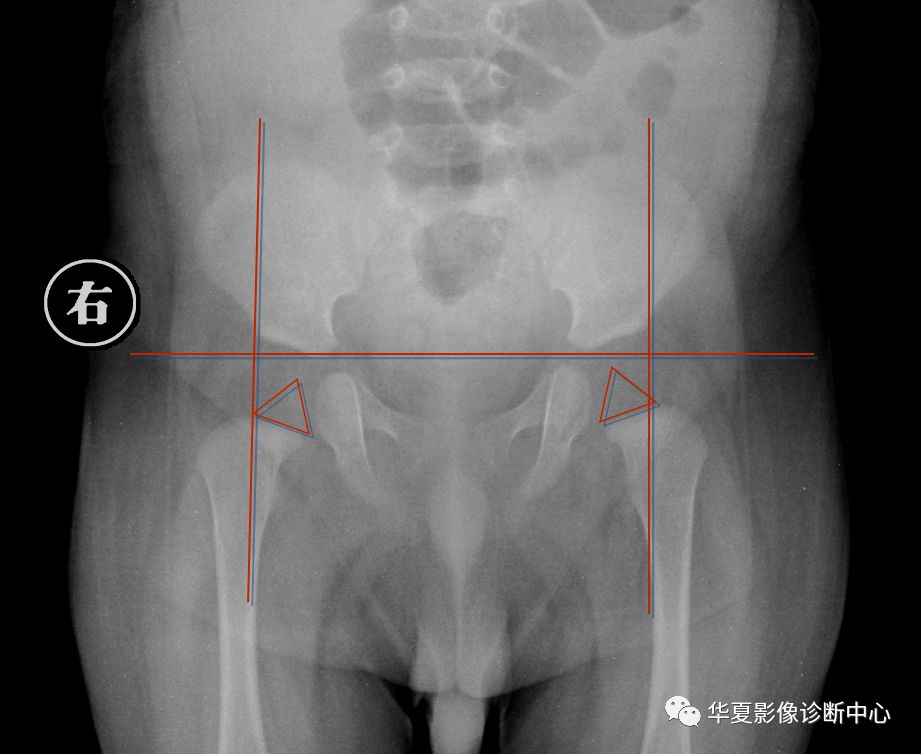

6. Shenton线:

正常闭孔上缘弧形线与股骨颈内侧弧形线相连在一个抛物线上,称为Shenton线,髋脱位、半脱位病例,此线完整性消失。

7.外侧线(Calve线)

外侧线(Calve线)即髂翼的外侧面与股骨颈外侧面的弧形连线,正常为连续的。